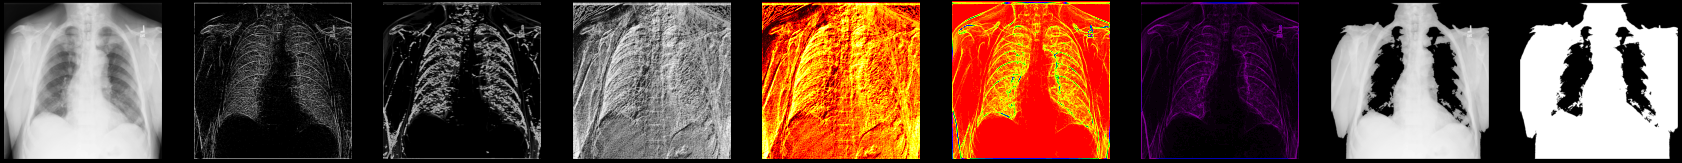

Let’s display some of the results of processed X-ray images you’ve worked with so far:

fig, axes = plt.subplots(nrows=1, ncols=9, figsize=(30, 30))

axes[0].set_title("Original")

axes[0].imshow(xray_image, cmap="gray")

axes[1].set_title("Laplace-Gaussian (edges)")

axes[1].imshow(xray_image_laplace_gaussian, cmap="gray")

axes[2].set_title("Gaussian gradient (edges)")

axes[2].imshow(x_ray_image_gaussian_gradient, cmap="gray")

axes[3].set_title("Sobel (edges) - grayscale")

axes[3].imshow(xray_image_sobel, cmap="gray")

axes[4].set_title("Sobel (edges) - hot")

axes[4].imshow(xray_image_sobel, cmap="hot")

axes[5].set_title("Canny (edges) - prism)")

axes[5].imshow(xray_image_canny, cmap="prism")

axes[6].set_title("Canny (edges) - nipy_spectral)")

axes[6].imshow(xray_image_canny, cmap="nipy_spectral")

axes[7].set_title("Mask (> 150, noisy)")

axes[7].imshow(xray_image_mask_noisy, cmap="gray")

axes[8].set_title("Mask (> 150, less noisy)")

axes[8].imshow(xray_image_mask_less_noisy, cmap="gray")

for i in axes:

i.axis("off")